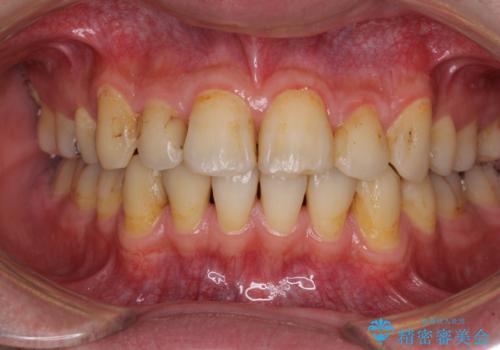

- 以前矯正を行った際に前歯が虫歯だらけとなり、審美面を気にして来院された患者様です。

虫歯の大きかった左右犬歯はオールセラミッククラウンで補綴治療をおこない、4前歯は研磨や古い充填物の詰め直しを行いました。

歯並びは良くなったものの、着色が気になって口元を見せることを躊躇していた用ですが、治療後は他人の視線を気にすることがなくなったようで、大変満足していただきました。